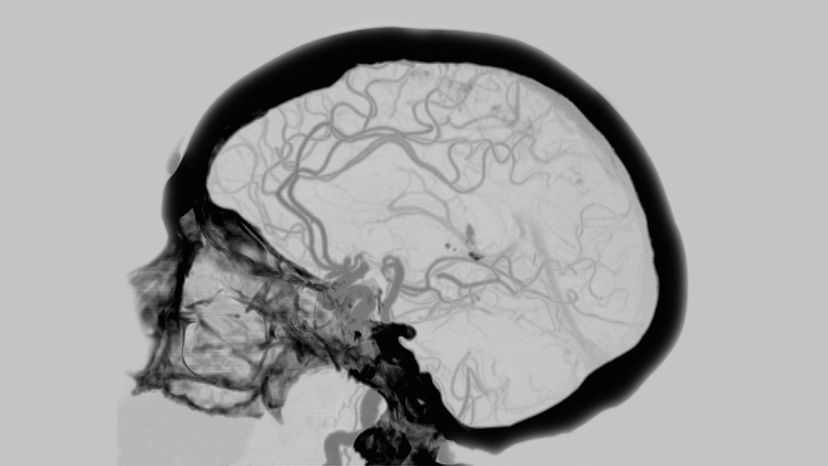

For instance, walking upright allowed us to better use our hands, but it also leads to back pain, knee problems and foot aches. Our large brains, combined with our narrow hips, resulted in a more arduous birthing experience and the necessity of such helpless young.

Now, an August 2018 study published in The American Journal of Human Genetics suggests that neuropsychiatric diseases such as schizophrenia and bipolar disorder might be evolutionary byproducts, too. These disorders are heritable and occur in roughly 3 percent of the human population, reports the study. They do not occur in nonhuman species.

According to the Stanford University researchers behind the study, changes in genes controlling brain size, connectivity and function may have made the human mind as we know it today possible, while also opening the door for neural disorders. Of particular note is the CACNA1C gene, which belongs to a family of genes responsible for making calcium channels that support cells in multiple ways. On this gene, highly repeated sequences of DNA displayed abilities to activate gene expression and were tightly linked to genetic markers for bipolar and schizophrenia susceptibility.

As such, the researchers hypothesize that the expanded genetic sequence in the CACNA1C gene may have given us an evolutionary advantage, while also opening the door to human-specific neuropsychiatric diseases. As ever, more work is required, but the results also could aid in the diagnosis and genotype-targeted treatment of schizophrenia and bipolar disorder.